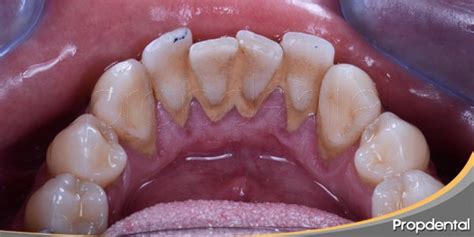

El sarro, también conocido como cálculo y tártaro dental, es la acumulación de calcio y fósforo sobre los dientes. Lo más frecuente es que el sarro aparezca en aquellos lugares del diente donde es más difícil limpiarse bien.

El sarro, conocido científicamente como cálculo dental, es una acumulación endurecida de placa bacteriana en los dientes. La placa es una mezcla pegajosa de bacterias, saliva y restos de alimentos que, si no se elimina adecuadamente, se mineraliza convirtiéndose en sarro. Este proceso se ve acelerado por sustancias en la saliva que facilitan la cristalización de los minerales.

Hay otro factor muy influyente en la formación del sarro. Las personas que tienen saliva con un pH más ácido son más propensas a las caries porque contribuye a debilitar el esmalte. Como hemos mencionado, el sarro es el endurecimiento de la placa dental, esta es una película incolora y pegajosa, formada por bacterias, proteínas y azúcares que se forma y adhiere sobre los dientes y muelas.

A diferencia de la placa bacteriana, el sarro dental no puede eliminarse con un buen cepillado, ya que siempre quedan restos. En primer lugar, el dentista hará uso de la punta de ultrasonidos para eliminar los depósitos de cálculo. Posteriormente, el higienista empleará la seda dental, pasándola por todas las superficies de las piezas. Además, aplicará tiras de pulir y la pasta de profilaxis, que eliminarán cualquier mancha superficial. Si el paciente presentase más resistencias, el odontólogo utilizará un aeropulidor con spray de bicarbonato. La profilaxis es un proceso totalmente indoloro para el paciente, que no requiere de anestesia. No obstante, en ocasiones, una profilaxis puede no ser suficiente para eliminar todo el sarro dental, especialmente si se acumula debajo de la línea de la encía. En estos casos, la persona podría padecer periodontitis.